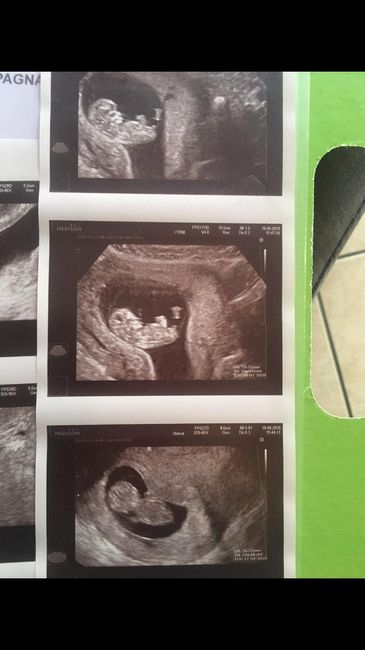

Metodo Ramzi... chi mi aiuta?!

Da Erika , Il 24 Luglio 2019 alle 08:26

Ragazze... inizio per dirvi che non è mia L ecografia... ma ve lo chiedo per conto di terzi 😊 siamo a 6+4 prima ecografia interna.... secondo voi cosa è?! Secondo me è...